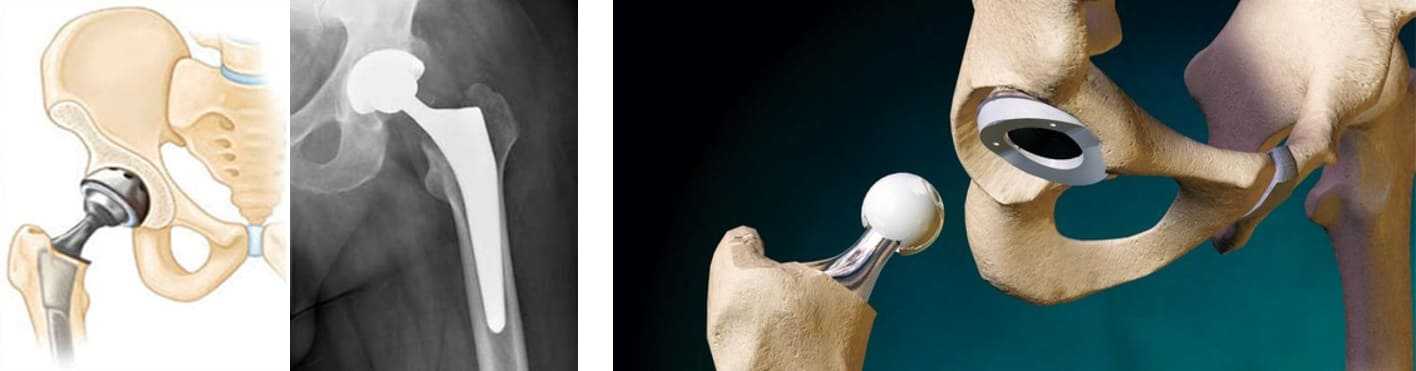

Замена таз сустава

Замена таз сустава 113 фотографий